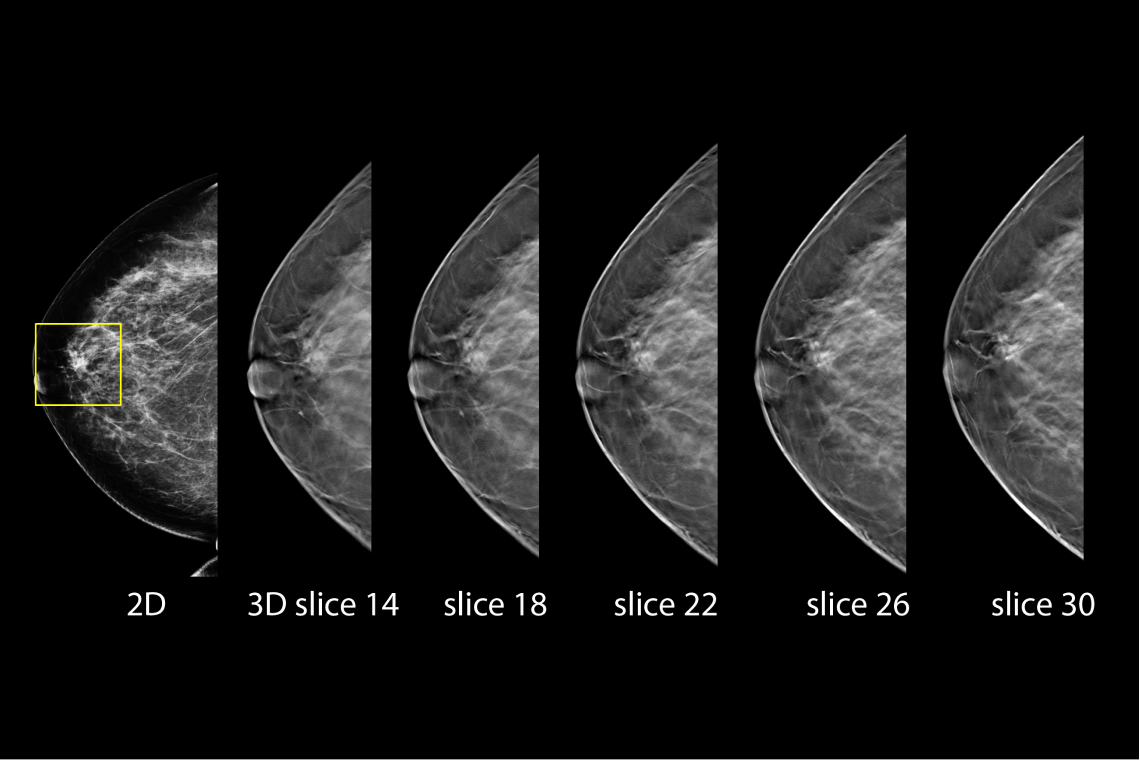

- Proven to detect 20%-65% more invasive breast cancers compared to 2D alone, an average increase of 41%.1

Hologic has further advanced breast cancer screening by producing 2D images from breast tomosynthesis data using C View software, resulting in a Low Dose Genius 3D Mammography exam with superior clinical performance compared with 2D alone.4

This Low Dose Genius 3D Mammography exam is performed in a rapid 3.7 second scan time for greater patient comfort and low patient dose, due to the elimination of 2D X ray exposures. The synthetic 2D images and 3D slices are reviewed together to make clinical decisions or diagnoses part of the Genius 3D Mammography screening exam.